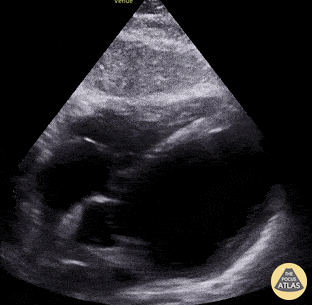

eingeschraenkte-lv